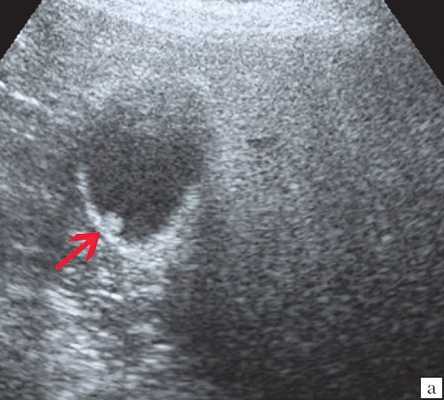

Ультрасонография является эффективным средством выявления полиповидной формы холестероза 7. Традиционной считается следующая сонографическая характеристика холестериновых полипов: неподвижные гиперэхогенные структуры, которые не дают акустической тени и прикрепляются к стенке желчного пузыря. Контуры таких образований, как правило, ровные, а размеры таких образований различны, чаще не превышают 10 мм (рис. 2).

a) Одиночный полип в желчном пузыре (гиперэхогенное пристеночное неподвижное образование, с ровными контурами, без акустической тени).

б) Одиночный полип в желчном пузыре.

в) Полиповидно-сетчатая форма холестероза, полипы размерами до 5 мм, повышенной эхогенности.

г) Одиночный полип в желчном пузыре.

Однако, по некоторым данным, размеры холестериновых полипов могут быть более 20 мм. Кроме того, полипы больших размеров (в 7% от общего числа) могут иметь пониженную эхогенность и фестончатый контур.

Мелкие холестериновые включения, образующие диффузную сеточку в толще подслизистого слоя размерами 1-2 мм, выглядят как локальное утолщение или уплотнение стенки желчного пузыря и в некоторых случаях (см. рис. 2) вызывают реверберацию (эхографический симптом "хвост кометы").